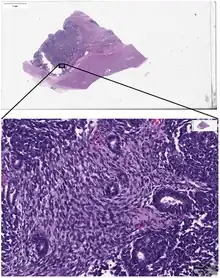

_stain_of_mixed_malignant_germ_cell_tumor_-_crop.png.webp)

Digital pathology has been approved by the FDA for primary diagnosis.[9] The approval was based on a multi-center study of 1,992 cases in which whole-slide imaging (WSI) was shown to be non-inferior to microscopy across a wide range of surgical pathology specimens, sample types and stains.[10] While there are advantages to WSI when creating digital data from glass slides, when it comes to real-time telepathology applications, WSI is not a strong choice for discussion and collaboration between multiple remote pathologists.[11] Furthermore, unlike digital radiology where the elimination of film made return on investment (ROI) clear, the ROI on digital pathology equipment is less obvious. The strongest ROI justification includes improved quality of healthcare, increased efficiency for pathologists, and reduced costs in handling glass slides.[12]